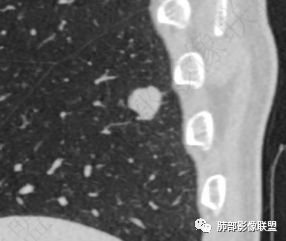

男,51。右肺下叶孤立实性结节,边界清,边缘少许磨玻璃,周围气肿带,浅分叶,平扫内见点状低密度,强化不明显。考虑良性结节,错构瘤>炎性肉芽肿鉴别腺癌。

右下叶胸膜下结节,轻分叶,结节内可见低密度区,CT值一83Hu,结节周围见空气新月征(黑边征),结节膨胀性生长,收缩力差,轻度强化,体检发现,综合分析,考虑错构瘤,但多个层面显示结节周围有边缘清楚的磨玻璃影,不知是否与层厚有关,有似清非清的感受,鉴别排除一下低分化腺癌

常表面光滑,可有浅分叶或无分叶,无毛刺,对周围肺组织无牵拉;常挂枝头(挂在肺动脉枝头上),很少到达胸膜。出现脂肪成分,或者典型的爆米花样钙化几乎可以确诊,软骨型错构瘤因软骨组织多,强化弱。平滑肌型错构瘤增强有一定强化。病灶周围边界清楚,常有很低密度的黑晕。

孤立性纤维性肿瘤

多起自脏层胸膜,表面光滑,强化多均匀,部分肿瘤内部可见蛇纹状血管(本例起病部位不符合)

综上所述,错构瘤可能性最大